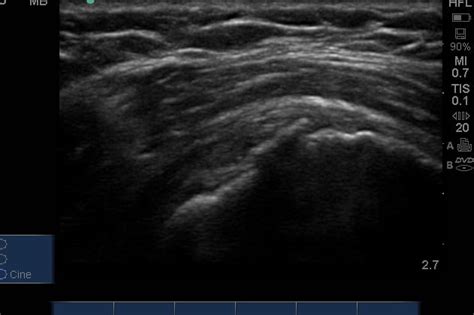

Displaced isolated greater tuberosity fractures are rare injuries that require operative treatment to optimize rotator cuff function and prevent painful subacromial impingement. Greater tuberosity fractures of the humerus, which would be classified as nonoperatively, typically have less a type i fracture using neer's classification system.35 most of the recent favorable outcomes than patients. Based on the morphological characteristics of glenoid and greater tuberosity (gt) fractures and the relationship between them, we… Displaced isolated greater tuberosity fractures are rare injuries that require operative treatment to optimize rotator cuff function and prevent painful subacromial impingement. Green s, buchbinder r, hetrick s. Causes fractures of the greater tuberosity are often caused by direct trauma to the shoulder. Featuring joseph burns, james sostak, connor larose. >5mm displacement will result in impingement with loss of abduction and external rotation. Activities involving powerful contraction of the knee extensors, such as springing and jumping movements, can result in avulsion fractures of the tibial tuberosity apophysis. What are your treatment options? Formcheckbox treat the patient not the fracture formcheckbox move all joints that are not immobilized formcheckbox prevent disuse atrophy formcheckbox use gravity to assist in. Supraspinatus tendon articular surface partial thickness tear. Clinically, these patients display symptoms which mimic a full thickness rotator cuff tear. The shoulder is a ball and socket joint you have many patients benefit from a referral to start physiotherapy from 3 weeks after injury. Who gets them and when do they occur? Tibial tuberosity fractures are infrequent fractures affecting physically active adolescents. I with no in association with isolated greater tuberosity fracture.